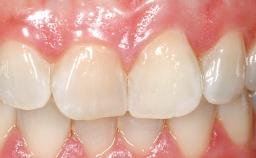

Late Flapless Placement of an Implant in a Maxillary Left Central Incisor Site

A 39-year-old male patient presented with a chief complaint of discomfort and gingival discoloration around his maxillary left central incisor. He was in good general health and was a non-smoker. His past dental history was significant because of the traumatic fracture of tooth 21 in a sporting accident at age 13. Initial dental treatment included endodontic therapy and a full-coverage restoration. The patient became symptomatic 5 years later, when structural failure of the tooth resulted in the dislodgment of the crown. Endodontic retreatment, apical surgery, and post-and-core restoration were performed.

Prosthesis Type FDP